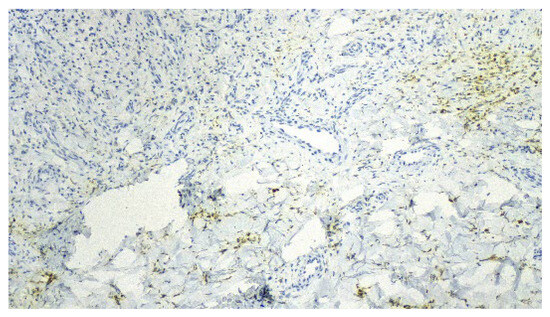

Collision Tumor of Angioimmunoblastic T-Cell Lymphoma and Kaposi Sarcoma in an HIV-Negative Elderly Woman: The First Reported Case in Asia

by Myung-Won Lee and Jin-Man Kim

Diagnostics 2025, 15(18), 2411; https://doi.org/10.3390/diagnostics15182411 - 22 Sep 2025

Background/Objectives: Angioimmunoblastic T-cell lymphoma (AITL) is a rare peripheral T-cell lymphoma of follicular helper T-cell (TFH) origin, often associated with immune dysregulation and EBV-positive B-cell proliferation. Kaposi sarcoma (KS) is a vascular neoplasm caused by human herpesvirus 8 (HHV-8), typically arising in immunocompromised [...] Read more.

Background/Objectives: Angioimmunoblastic T-cell lymphoma (AITL) is a rare peripheral T-cell lymphoma of follicular helper T-cell (TFH) origin, often associated with immune dysregulation and EBV-positive B-cell proliferation. Kaposi sarcoma (KS) is a vascular neoplasm caused by human herpesvirus 8 (HHV-8), typically arising in immunocompromised individuals. The synchronous occurrence of AITL and KS in HIV-negative patients is exceptionally rare, with only three cases previously reported worldwide. Case Presentation: We describe an 81-year-old HIV-negative Korean woman presenting with progressive generalized edema and dyspnea. Imaging revealed multifocal lymphadenopathy. Excisional biopsy of the inguinal lymph node showed two distinct but adjacent neoplastic processes. The AITL component demonstrated a polymorphous infiltrate of atypical TFH cells expressing CD3, CD4, CD10, PD-1, and Bcl-6, with monoclonal TCR-γ rearrangement and TET2 and RHOA mutations. The KS component comprised spindle cells with slit-like vascular spaces, red blood cell extravasation, and immunoreactivity for HHV-8, CD31, CD34, and ERG. The findings were consistent with a collision tumor. Despite supportive care, the patient’s condition deteriorated, and she was discharged with palliative care. Discussion: The coexistence of AITL and KS in an HIV-negative setting raises important pathogenetic considerations. AITL is characterized by profound immune dysregulation, with depletion of normal T-cell subsets, abnormal B-cell activation, and cytokine milieu changes that may favor latent viral reactivation. This immunologic environment may permit HHV-8 reactivation, thereby facilitating the development of KS even in the absence of overt immunodeficiency due to HIV infection. Our findings support the hypothesis that AITL-related immune dysfunction may create a permissive niche for HHV-8-driven neoplasia. Conclusions: This is the first reported case in Asia and the fourth worldwide of a collision tumor comprising AITL and KS in an HIV-negative patI dient. The case suggests that AITL-associated immune dysregulation may facilitate HHV-8 reactivation and KS development even in the absence of HIV infection. Awareness of this association is critical for accurate diagnosis and optimal patient management. Full article